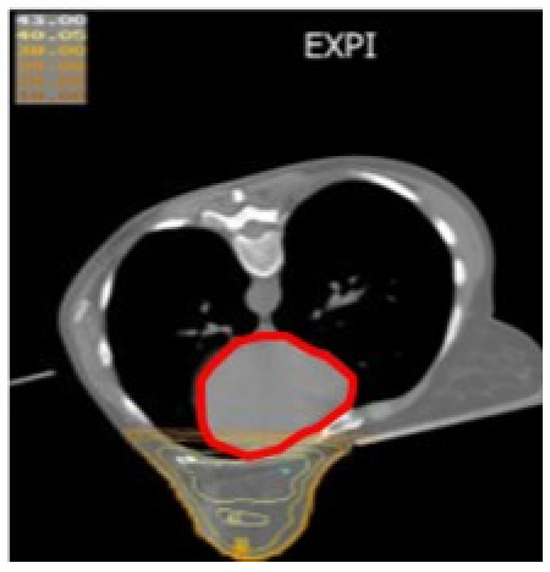

The Prone-Position Whole Breast Irradiation Paradox: Where Do We Stand? A Comprehensive Review

by Chris Monten, Ilaria Benevento, Antonietta Montagna, Edy Ippolito, Paola Anselmo, Luciana Rago, Barbara D’Andrea, Angela Solazzo, Antonella Bianculli, Raffaele Tucciariello, Giammaria Fiorentini, Vito Metallo, Simone Salvago, Carmen Santoro, Anna Vallario and Grazia Lazzari

Over the past two decades, interest in prone-position whole breast irradiation (WBI) as an effective and practical alternative to supine treatment has been growing a lot. Although solid scientific data has provided evidence of substantial dosimetric benefit with decreased toxicity, there is still [...] Read more.

Over the past two decades, interest in prone-position whole breast irradiation (WBI) as an effective and practical alternative to supine treatment has been growing a lot. Although solid scientific data has provided evidence of substantial dosimetric benefit with decreased toxicity, there is still conflict in the radiotherapy community over whether to adopt prone-position WBI as a valid alternative to supine radiotherapy (RT) in routine clinical practice. A large number of prone trials have been conducted to assess and address concerns related to prone treatment in large and pendulous breasts and in left and right breast cancer (BC), nodal irradiation, and its reproducibility with deep inspiration breath hold (DIBH) delivery with photons or protons. Appropriate atlases have been defined to improve prone nodal irradiation. Additionally, more comfortable customized immobilization couches have been constructed to permit IMRT beams and VMAT arrangements with modern LINACs. Although our search in literature databases shows a growing body of evidence from the past two decades on this issue, prone WBI is still underused. Given the paradox of the advances and benefits of this positioning and the lack of drive in the radiotherapy community towards its clinical implementation, the purpose of this comprehensive review is to evaluate the true advantages of this position in real life and contextualize it in scenarios like large breasts, left-sided breast cancer, and nodal irradiation to encourage its implementation in clinical practice. Full article

Show Figures

Figure 1